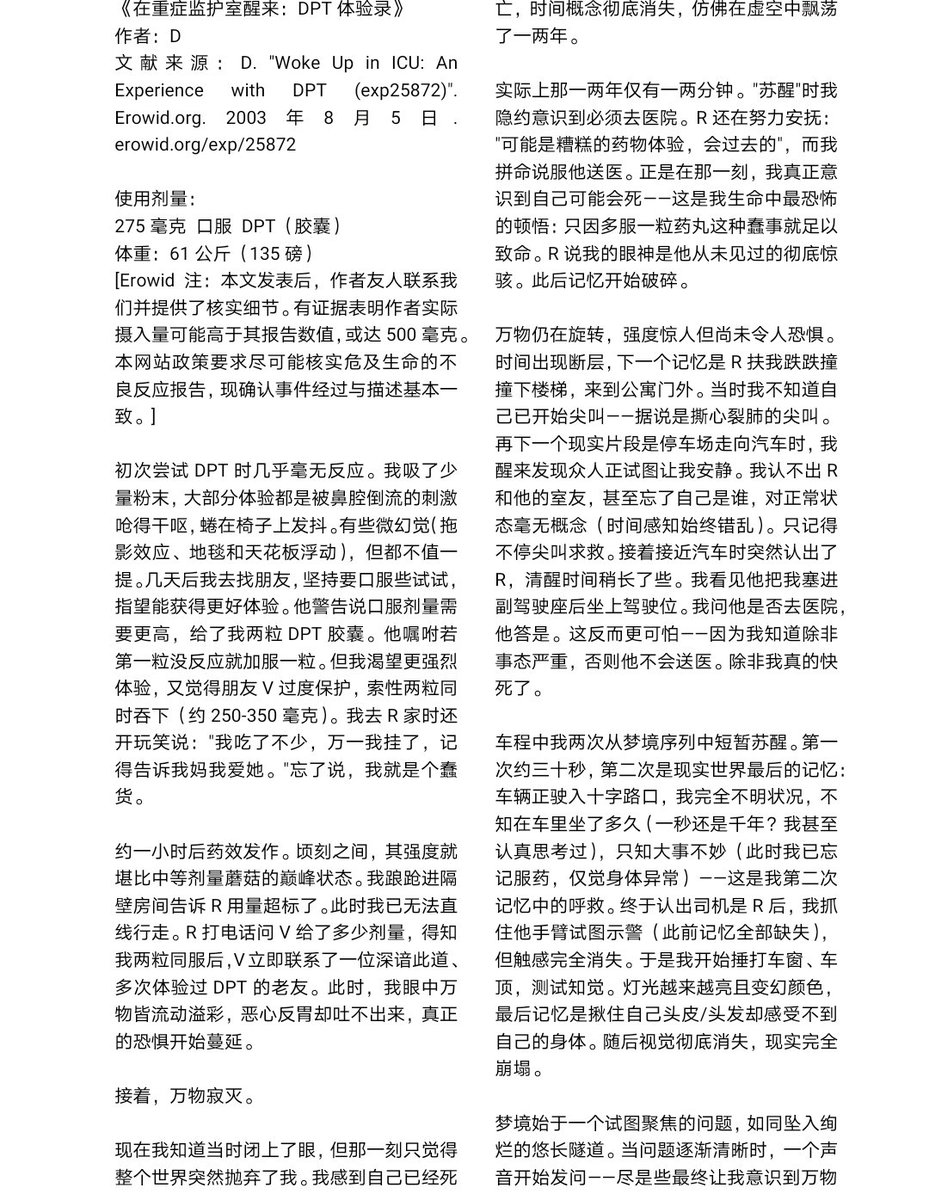

TEST FROPOFOL

果然蝴蝶针会翻车,太难用了。

最后用了留置针,推2ml.

本来是1ml,但忘记关闸血液回流,我怕把针管堵了于是又推了1ml

*我竟然无师自通留置针了!用的肘静脉因为其他地方被蝴蝶针霍霍了

提前推了利多卡因(也是测试倒抽)所以毫无痛感,耶

配合另一种麻醉就可以无痛重开了(bushi) https://t.co/Uj139Q2tBk

炽烈已极 @AnIncandescence竟然能在50mg下撑那么久,意志力比我想的还要强大,但是乱七八糟。

手上都是血迹不说,周围的其他地方也有我意料之外的血迹